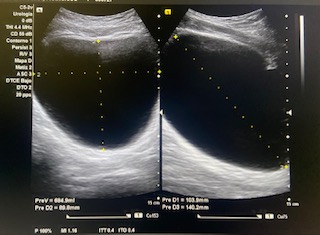

Vejiga bien repleccionada sin alteraciones a simple vista.

Volumen residual: 243 ml. Próstata de contornos regulares y ecogenicidad homogénea a simple vista. Volumen prostático: 49 cc.